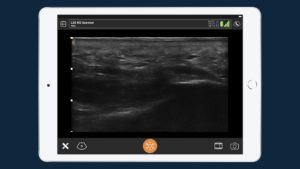

«With handheld ultrasound, we’re now able to complete many ultrasound exams, including cardiac ultrasound, lung ultrasound, and abdominal ultrasound. We’ve been using ultrasound in trauma for about 10 years, but now all of a sudden, we have a small handheld device that can be easily sterilized and kept clean so we can use it in the diagnosis of COVID-19 and quickly clean it between patients.»